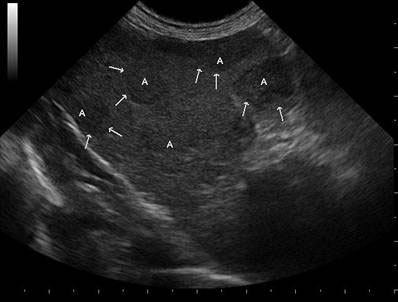

L'ecografia e l'ecocardiografia sono branche della diagnostica per immagini che utilizzano gli ultrasuoni per ottenere indagare organi ed apparati, con un ruolo fondamentale nell'iter diagnostico di molte patologie.

L'Ospedale degli Animali dispone di un ecografo di ultima generazione, fornito di modulo doppler ed eco-doppler e di vari tipi di sonde, che permette un esame completo ed accurato su diverse tipologie di pazienti e di strutture anatomiche.

Si eseguono ecografie addominali, ecografie toraciche, ecografie al collo, all'occhio e muscolo-tendinee, ecocardiografie, aghiaspirati e biopsie ecoguidate (procedure eseguite alla presenza di un anestesista).